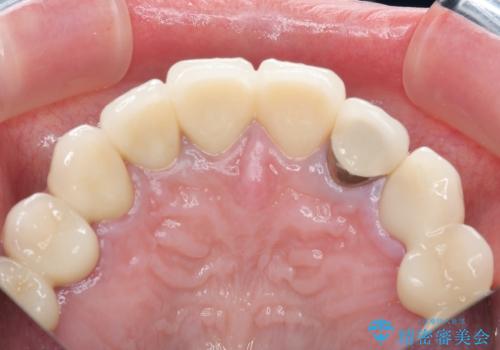

保険適応 硬質レジン前装冠から審美的でオールセラミッククラウンへ

10数年前に治療を行った保険適応の硬質レジン前装冠は変色劣化が進み、審美的に問題があるだけでなく虫歯のリスクも高くなり好ましくない状況です。

審美的かつ精度の高いセラミック治療を行うことで、汚れがつきにくく虫歯や歯周病の感染リスクを将来にわたって抑える治療が可能になります。

- 39.6万円(ジルコニアクラウン×3・仮歯×3)費用は治療当時の料金となります